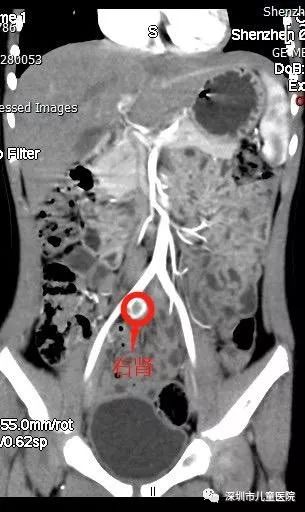

果不其然,这次,在她的右侧盆腔发现了一个蚕豆大小的、功能很微弱的肾脏。原来,小美的右肾并没有凭空消失,而是“跑”到了盆腔,在这里安了家。

至此,谜团终于被揭开了:

她的右肾发育不良,右肾异位(盆腔),右侧输尿管异位开口。 来,小美的右肾并没有凭空消失,而是“跑”到了盆腔,在这里安了家。